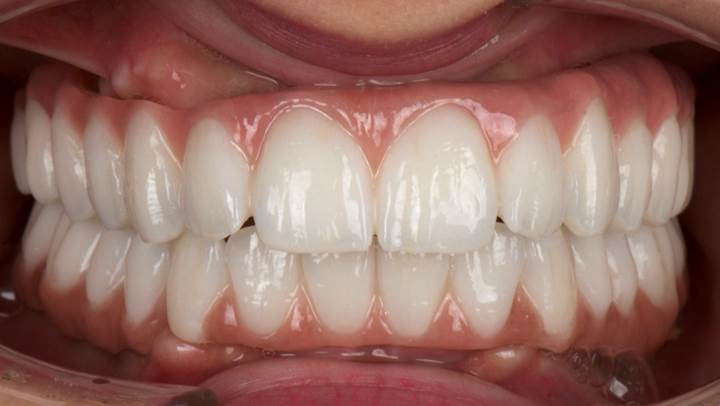

“AnyRidge ensures long-term biological stability

& functionality even in

full-mouth rehabilitation case. ”

Clinical case: Full-mouth implants for mandibular & maxilla - restored using mixed prostheses

- Courtesy of Dr. Hyun Jun Kim, Korea -